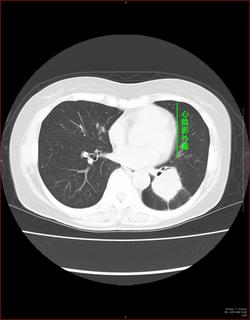

CTで見ると…

3Dだと、こうなります。

気管狭窄ですね。こういう所見もレントゲンで捉えることができるのです。